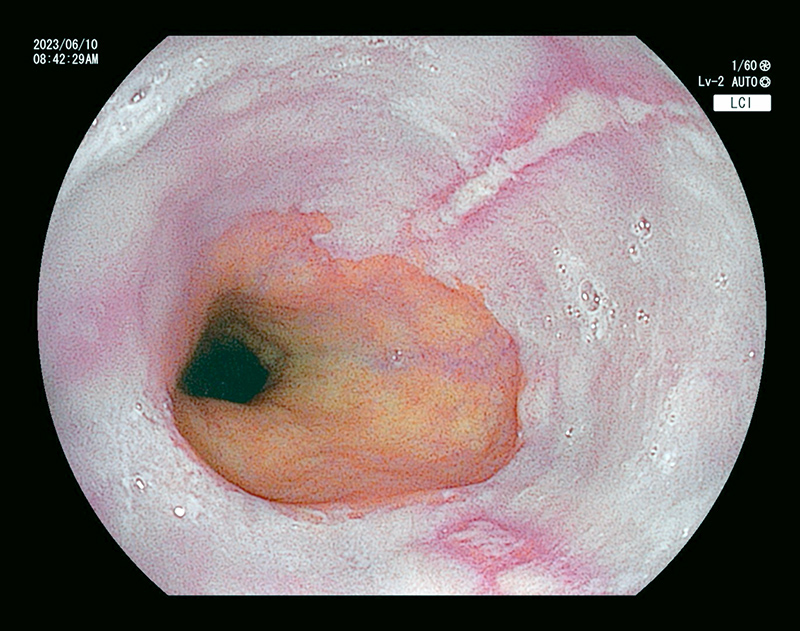

通常光では淡い発赤ですが

特殊光-1

同じところを空気量調整し特殊光LCIにて観察

特殊-2

同じところを特殊光BLIにて血管と表面構造を観察